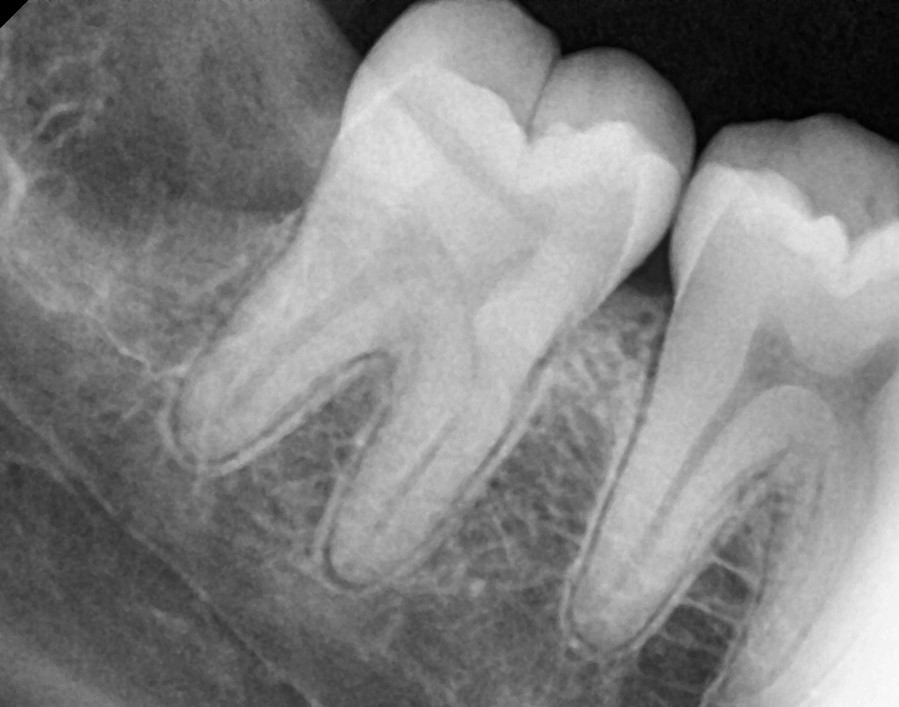

Vertical

After After

Before Before